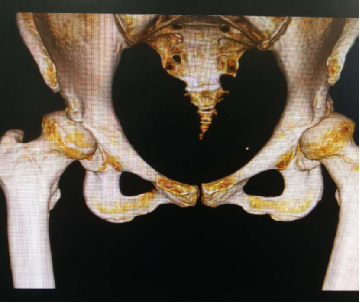

患者,女性,59岁。因“跛行30余年,加重并右髋部疼痛2年”来诊。体格检查:双下肢不等长,右侧髋关节深压痛,双侧髋关节活动受限,右侧显著;右髋关节活动度:屈80°,伸-10°;内收10°,外展20°;内旋:10°,外旋10°;双下肢无明显短缩。患者以右侧髋部疼痛、活动受限为主,左侧无明显疼痛感,给予行右侧全髋关节置换术治疗。

术前X线及髋关节CT图像显示,双侧髋臼明显发育不良,髋臼变浅,右侧髋臼骨质密度不均匀,双侧髋臼对股骨头的包容不足。